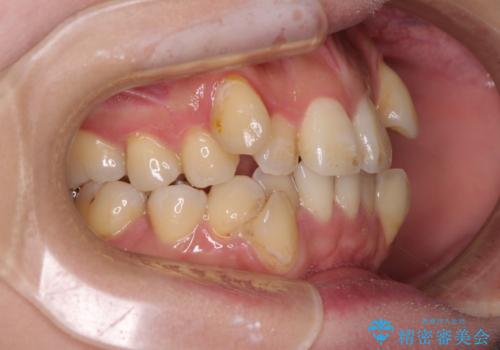

- 上下前歯のデコボコを気にして来院された患者様です。

デコボコが強いため、非抜歯で矯正をすると出っ歯仕上がりとなるため、上下左右の第一小臼歯4本を抜歯することとしました。